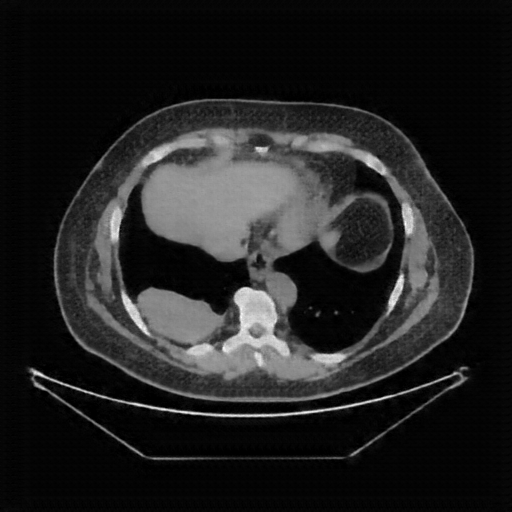

Image Grid

4Γ—3 grid: Rows show different image types (Original NATIVE, Reconstructed NATIVE, Original VENOUS, Generated VENOUS), Columns show windowing techniques (No Window, Lung Window, Mediastinum Window)

Reconstructed NATIVE CT scan (cycle consistency)

Full window (WL 1023.5, WW 4095 β†’ Low βˆ’1024, High +3071)